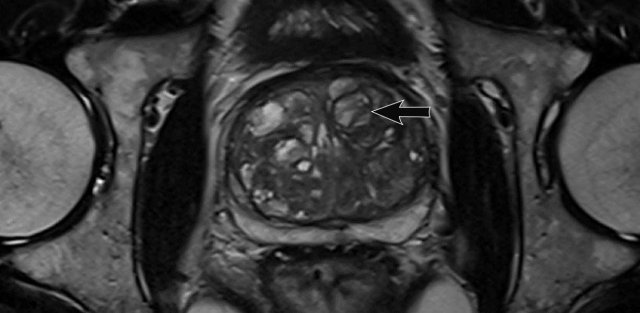

Benign prostate hyperplasia

Benign prostate hyperplasia (BPH) results in the formation of well-circumscribed, encapsulated nodules in the transition zone.

Some of these nodules have dense stroma with low T2W signal intensity and low ADC (yellow arrow).

The most important characteristic feature to distinguish BPH nodules from malignancy is the generally well-defined and well-circumscribed morphology interpreted in axial, coronal and sagittal series.

The left peripheral zone lesion was classified as PI-RADS 5 (red arrow).

MRI- targeted biopsy revealed a Gleason 3+4.

T2 hypointense BPH nodules can be less distinctly circumscribed within the transition zone and may show some degree of restricted diffusion.

Also, these nodules tend to enhance early and intensely on DCE, making conclusive characterization difficult.

Here a patient with BPH in the transition zone seen as heterogenous stroma with a large cystic area (arrow).

Biopsies showed chronic benign prostatitis.

Not all nodules exist in the transition zone.

Some can be ectopic and may be found in the peripheral zone (arrow).

This entity shouldn’t be confused with prostate cancer.

BPH consists of a mixture of stromal and glandular hyperplasia and may appear as band-like areas and/or encapsulated round nodules with circumscribed or encapsulated margins.

Image

This coronal T2W

image shows various types of BPH nodules.

- glandular nodule (blue circle)

- atypical nodule (yellow circle)

- nodule in nodule (various smaller nodules inside contained in a larger nodule) (green circle).

Predominantly glandular BPH nodules and cystic atrophy exhibit moderate-marked T2 hyperintensity and are distinguished from malignant tumors by their signal and capsule.